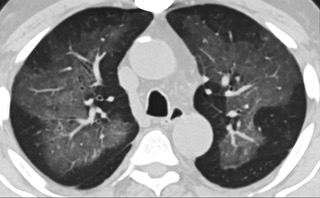

疑點一,電子煙患者的CT影像和臨床表現并不具有特異性。所謂美國電子肺炎患者,其實是對沒有其他合理診斷證據、吸食電子煙肺炎患者的統稱。這些患者在病發前90天內吸食了電子煙,尤其值得注意的是,部分患者的CT影像特征和臨床表現與病毒性肺炎患者極其相似。

中、下肺軸位CT平掃顯示毛玻璃樣混濁伴胸膜下保留。(同一病人CT影像)

中、下肺軸位CT平掃顯示毛玻璃樣混濁伴胸膜下保留(箭頭)。(同一病人CT影像)